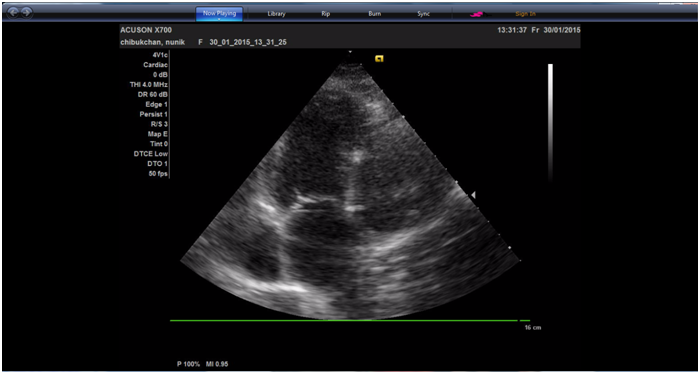

A 59 year-old female with a history of atrial fibrillation (AF), and arterial hypertension presented to CCU with respiratory insufficiency, palpitation and weakness. She had developed AF 2-3years earlier and was followed up at the outpatient clinic. She had been treated with warfarin at a dose that resulted in an international normalized ratio of 2.0 to 3.0. She was also taking beta-blocker, ACE inhibitor. Blood pressure at admission was 140/80 mm Hg, blood oxygenation was 90-92%. Electrocardiography showed atrial fibrillation with the ventricular rate of 90-100 per minute. Transthoracic echocardiography revealed a giant (7 x 8cm) left atrial (LA) diverticulum with big (5 x 6cm) thrombus inside (Figure 1). Systolic function of the left ventricle (LV) was preserved; LV ejection fraction was 50%. The diverticulum was compressing the left atrium and left ventricle lateral wall.

Figure 1 Transthoracic echocardiographic apical four-chamber view demonstrating the diverticulum interconnected with the left atrium.